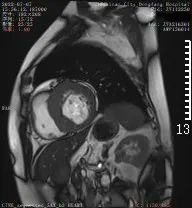

心脏磁共振检查

正式开展心脏磁共振(CMR)检查

是除心脏彩超、冠脉CTA之外的

另一种先进检查技术

具有无X线辐射、任意平面成像的优势

是集形态、灌注、功能及分子成像

于一体的成像技术

心脏磁共振能够对

心肌病、冠心病、先心病

心脏瓣膜病、心包疾病、心脏肿瘤

等病变进行诊断及鉴别诊断

在心脏形态与功能、心肌评估中

具有优势

对淀粉样心肌病、致密化不全心肌病等

具有独特诊断优势

半个月的时间,东方总院

已成功检查和诊断心脏病变3例